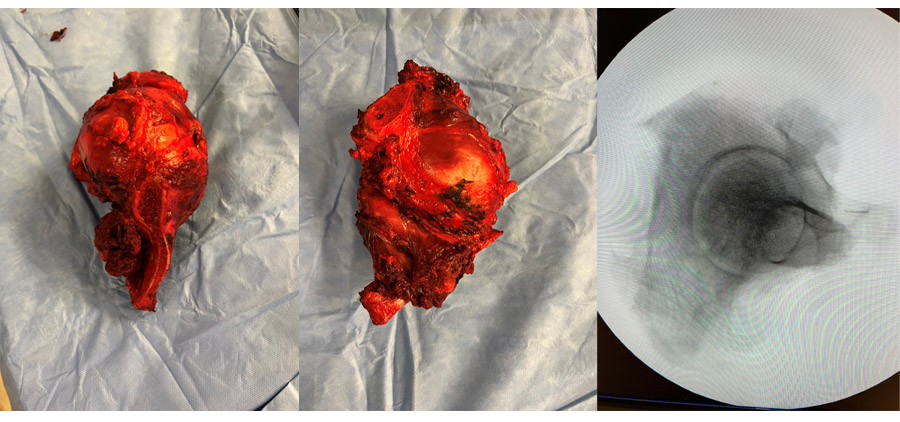

During the operation: Clinical and radiological images of the removed cancerous joint tissue.